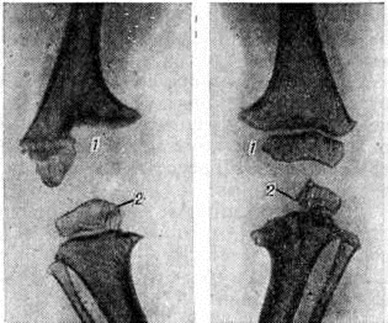

Своеобразно протекает гематогенный Остеомиелит в раннем детском возрасте, обычно развивающийся в первые недели или месяцы жизни при сепсисе. Как правило, поражается сразу несколько костей в результате гематогенного возникновения нескольких эпифизарных костных очагов, вследствие чего заболевание получило название эпифизарного Остеомиелит (рисунок 6). Обычно поражаются проксимальные эпифизы плеча, бедра, эпифизы костей, сочленяющихся в коленном суставе. Воспаление быстро распространяется на сустав. Этот тяжёлый остеоартрит (смотри полный свод знаний) практически никогда не заканчивается анкилозом, даже при обширных костных разрушениях, а восстановление костей бывает практически полным. Если не происходит прорыва гнойника через кожные покровы, то эпифизарный Остеомиелит может остаться диагностированным. Его последствия нередко обнаруживаются только в более позднем возрасте и могут быть истолкованы не всегда правильно, например, как врождённый подвывих или вывих.

Рис. 6.

Рентгенограмма коленных суставов ребёнка, больного эпифизарным остеомиелитом: разрушены эпифизы бедренных (I) и большеберцовых (2) костей; видна деформация суставов.